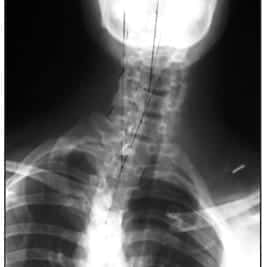

Strong Extension-Based Exercise of the Cervical Spine – A Case Series

Click here to read article as it originality appeared in the CBP™ Journal INTRODUCTION In a recent paper published in the Journal of Rheumatology, the Cervical Overview Group conducted a large-scale meta-analysis of existing literature concerning the management of mechanical neck disorders, including radiculopathy(1). The categories of evidence ranged fromstrong evidence, to moderate evidence, to…